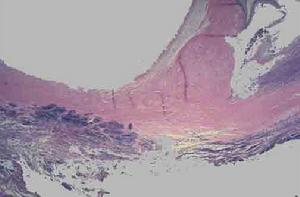

亞急性感染性心內膜炎贅生物所附著的瓣膜有炎性反應及灶性壞死,其周邊有淋巴細胞,纖維細胞及巨細胞浸潤。壞死細胞周圍有新生毛細血管,結締組織及肉芽組織,當炎症消退,贅生物纖維化,表面為內皮細胞所覆蓋,經治療痊癒的病例,三個月才能完全癒合,未治癒的病例,癒合與炎症反應交叉存在。贅生物大而易碎,脫落可致臟器及周圍動脈栓塞,如腎、腦、脾、腸系膜及四肢等,先心病並感染性心內膜炎病例,多並發肺栓塞,局部細菌滋長可使瓣葉產生潰瘍或穿孔,腱索及乳頭肌斷裂及細菌性動脈瘤。抗原-抗體複合物在腎血管球沉積,可發生腎血管球性腎炎,由於免疫反應引起小動脈內膜增生,阻塞及小血管周圍炎,表現為皮膚及黏膜的淤點,發生於手指、足趾末端的掌面,稍高於皮面,有壓痛,5-15mm大小,稱奧氏(Osler)結節,後掌及足趾有數毫米大小的紫紅色斑點,稱為Janeway氏結節。